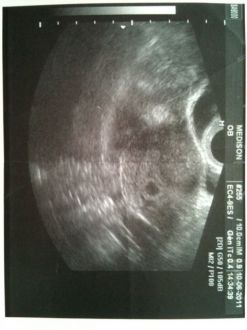

Voila une petit écho de notre fils !!

Bébé va très bien, il pèse déjà 500g mesure a peu près 20 cm! Il bouge très bien !! il avait les jambes croisées et les bras derrière la tête tranquille enfaite !

Nous allons être les heureux parents d'un petit garçon !!!